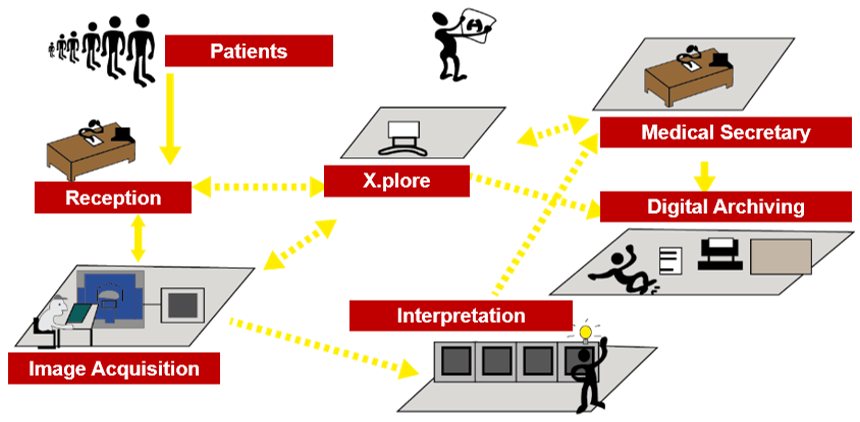

Here we can see the work organization after the RIS-PACS integration. In fact, PACS is used by radiology personnel to manage the workflow of patient exams:

This simplified diagram indicates the image data flow between the imaging modality and PACS.

PACS is usually an integration of input from digital devices which may be any radiological modality. These devices include Image acquisition device, image storage server for short or long term storage of data, transmission network, display station, imaging work station, and user interface, camera to convert to hard copies images on a need basis, and integration to radiology information system and hospital information system.

This simplified diagram indicates the image data flow between the imaging modality and PACS.

- Flow: Modalities -> PACS

The flow of “raw” format images. Acquisition protocol for each modality (automation and technologist dependent).